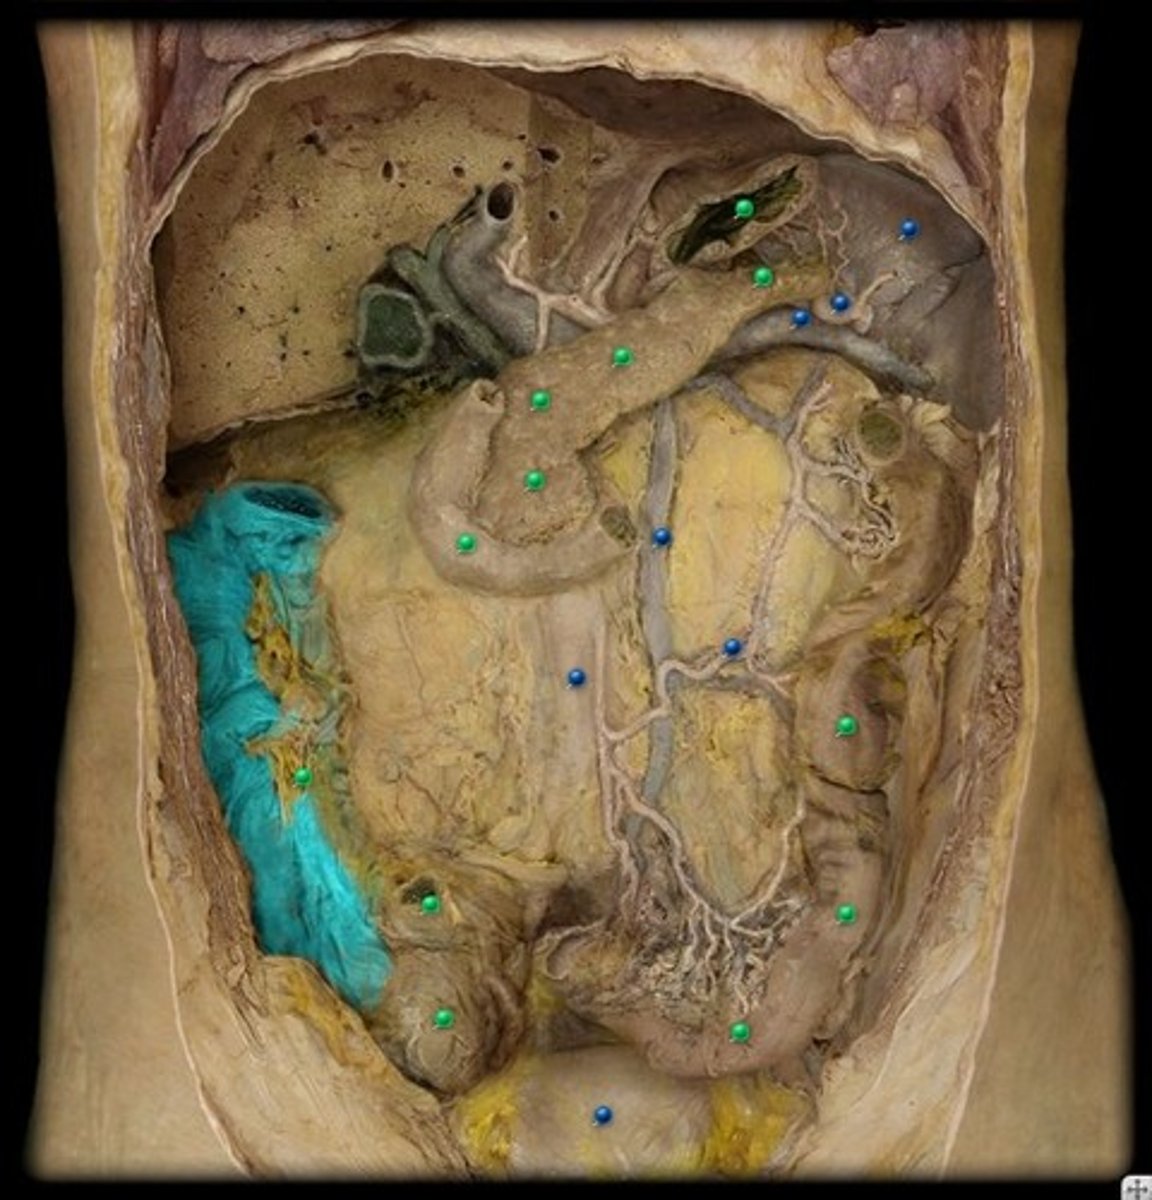

GI anatomy pin test

128 Terms

superior mesenteric artery

jejunal and ileal arteries

ileocolic artery

right colic artery

middle colic artery

inferior mesenteric artery

left colic artery

sigmoidal arteries

marginal artery